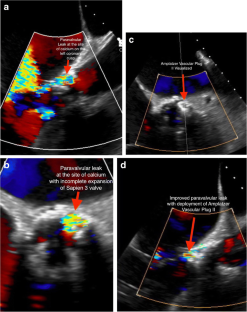

Fig. 1